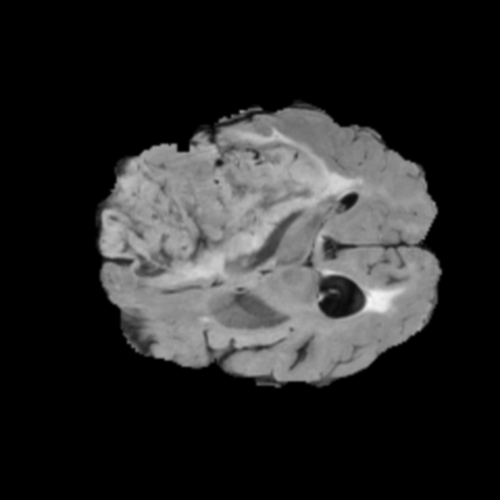

Ejemplos de Modalidades MRI

Visualización de las 4 modalidades de resonancia magnética y las segmentaciones de zonas tumorales utilizadas para entrenar el modelo

Glioma de Alto Grado (HGG)

FLAIR HGG

FLAIR

T1ce HGG

T1ce

T2 HGG

T2

T1 HGG

T1

Núcleo HGG

Núcleo

Edema HGG

Edema

Realce HGG

Realce

Tumor Completo HGG

Tumor Completo

Núcleo Edema Realce